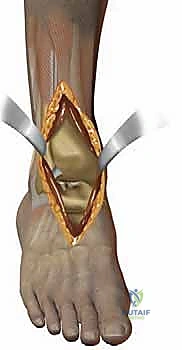

يتكون مفصل الكاحل الأساسي (المفصل الظنبوبي الكاحلي - Tibiotalar joint) من التقاء ثلاث عظام رئيسية:

1. عظمة الظنبوب (Tibia): وهي عظمة الساق الكبرى، وتشكل السقف والجزء الداخلي من الكاحل (الكعب الداخلي - Medial Malleolus).

2. عظمة الشظية (Fibula): وهي عظمة الساق الصغرى، وتشكل الجزء الخارجي من الكاحل (الكعب الخارجي - Lateral Malleolus).

3. عظمة الكاحل (Talus): وهي العظمة السفلية التي تستقر داخل التجويف الذي تشكله عظمتا الساق، وتعمل كنقطة ارتكاز محورية للقدم.

تُغطى نهايات هذه العظام بطبقة ناعمة ومرنة تسمى "الغضروف المفصلي" (Articular Cartilage). هذا الغضروف يعمل كوسادة ممتصة للصدمات ويسمح للعظام بالانزلاق فوق بعضها البعض باحتكاك يكاد يكون معدوماً. علاوة على ذلك، يُفرز المفصل سائلاً زلالياً (Synovial Fluid) يعمل كزيت تشحيم لضمان نعومة الحركة. عندما يتضرر هذا الغضروف لأي سبب، تبدأ العظام بالاحتكاك المباشر، مما يسبب الألم الشديد، التورم، وفقدان القدرة على الحركة؛ وهنا تبرز الحاجة الماسة للتدخل الطبي.